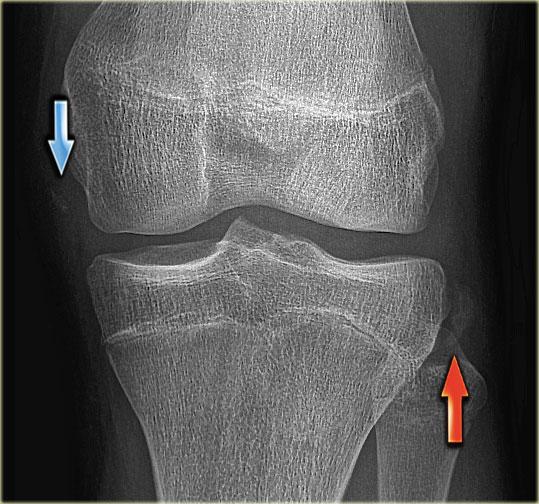

Gãy xương Segond và rách sụn chêm

Gãy xương Segond là tổn thương bong gân (avulsion) của dây chằng bao khớp bên ngoài.

Cơ chế chấn thương là xoay trong kết hợp với lực varus.

Trên phim X-quang, tổn thương biểu hiện dưới dạng một mảnh xương hình bầu dục tách rời khỏi mặt ngoài đầu gần xương chày (hình).

Gãy xương Segond có mối liên quan chặt chẽ với rách dây chằng chéo trước (75-100%) và tổn thương sụn chêm trong và ngoài (66-70%).

Trên phim X-quang, gãy xương Segond có thể dễ bị bỏ sót (mũi tên đỏ).

Lưu ý rằng còn có thêm tổn thương bong gân của dây chằng bên trong.

Bên trái là hình chụp tư thế AP của một bệnh nhân khác.

Kết hợp với gãy xương Segond (mũi tên đỏ), còn có thêm gãy bong điểm bám của dây chằng chéo trước (mũi tên xanh).